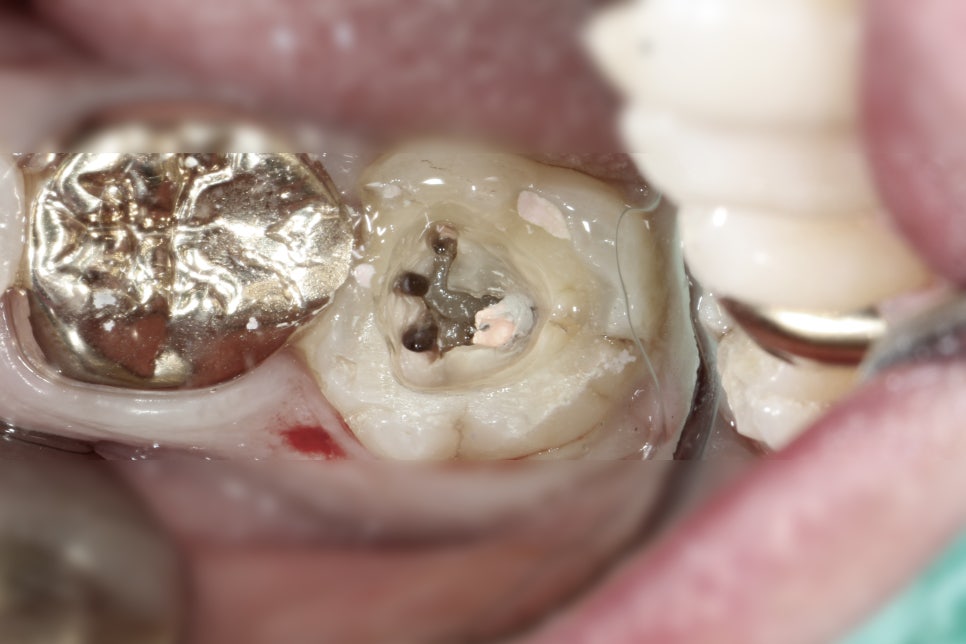

그리고 이건 창피하지만 올려본다.. CF하는 도중에 뭔가 이상해서 와동 확장 해서 메지알 캐널 하나 더 찾고 사진 찍고 마무리 한 뒤에 코어 축성까지 했는데, 들어와서 사진 보고 케이스 복기하는 중에야 DL missing이 보인다.. floor와 wall사이에 틈도 보이고. 이미 환자분은 귀가했지. 다음 내원에 코어 파내고 확장 해야겠다 ㅠㅠ 아 진짜🤦♂️ 할많하않이다.